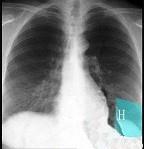

问题 如图所示正常胸部X线影像图像上,该英文字母所代表的肺段为 ( )

选项 A.H代表内基底段 B.H代表前基底段 C.H代表外基底段 D.H代表后基底段 E.H代表背段

答案 C